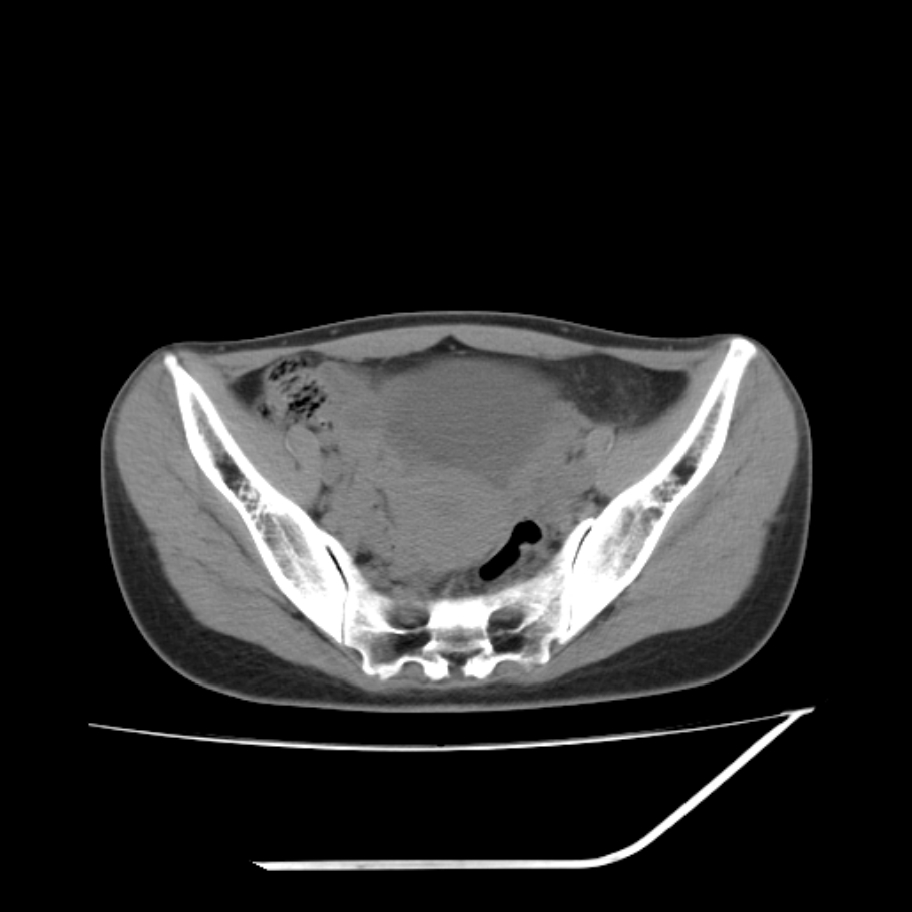

女,25岁。偶尔有右下腹不适感,余无明显异常。(结婚半年),囊壁较厚,是卵巢囊肿吗?

其上一层面见两枚小气泡影,考虑为肠管影可能,不完全除外囊肿

右侧卵巢区椭圆形囊性肿物,内壁光滑 无分隔。直肠子宫间隙内有少量积液征象。结合临床考虑卵巢巧克力囊肿,还要问问有没有痛经,本例ct怎么没有灌肠?要是灌肠或前一前口服造影剂,起码可以和肠管区别开

考虑右侧卵巢囊性占位性病变(巧克力囊肿?),盆腔积液有不排除宫外孕可能,请结合临床和b超。

右侧卵巢囊伴盆腔少量积液。